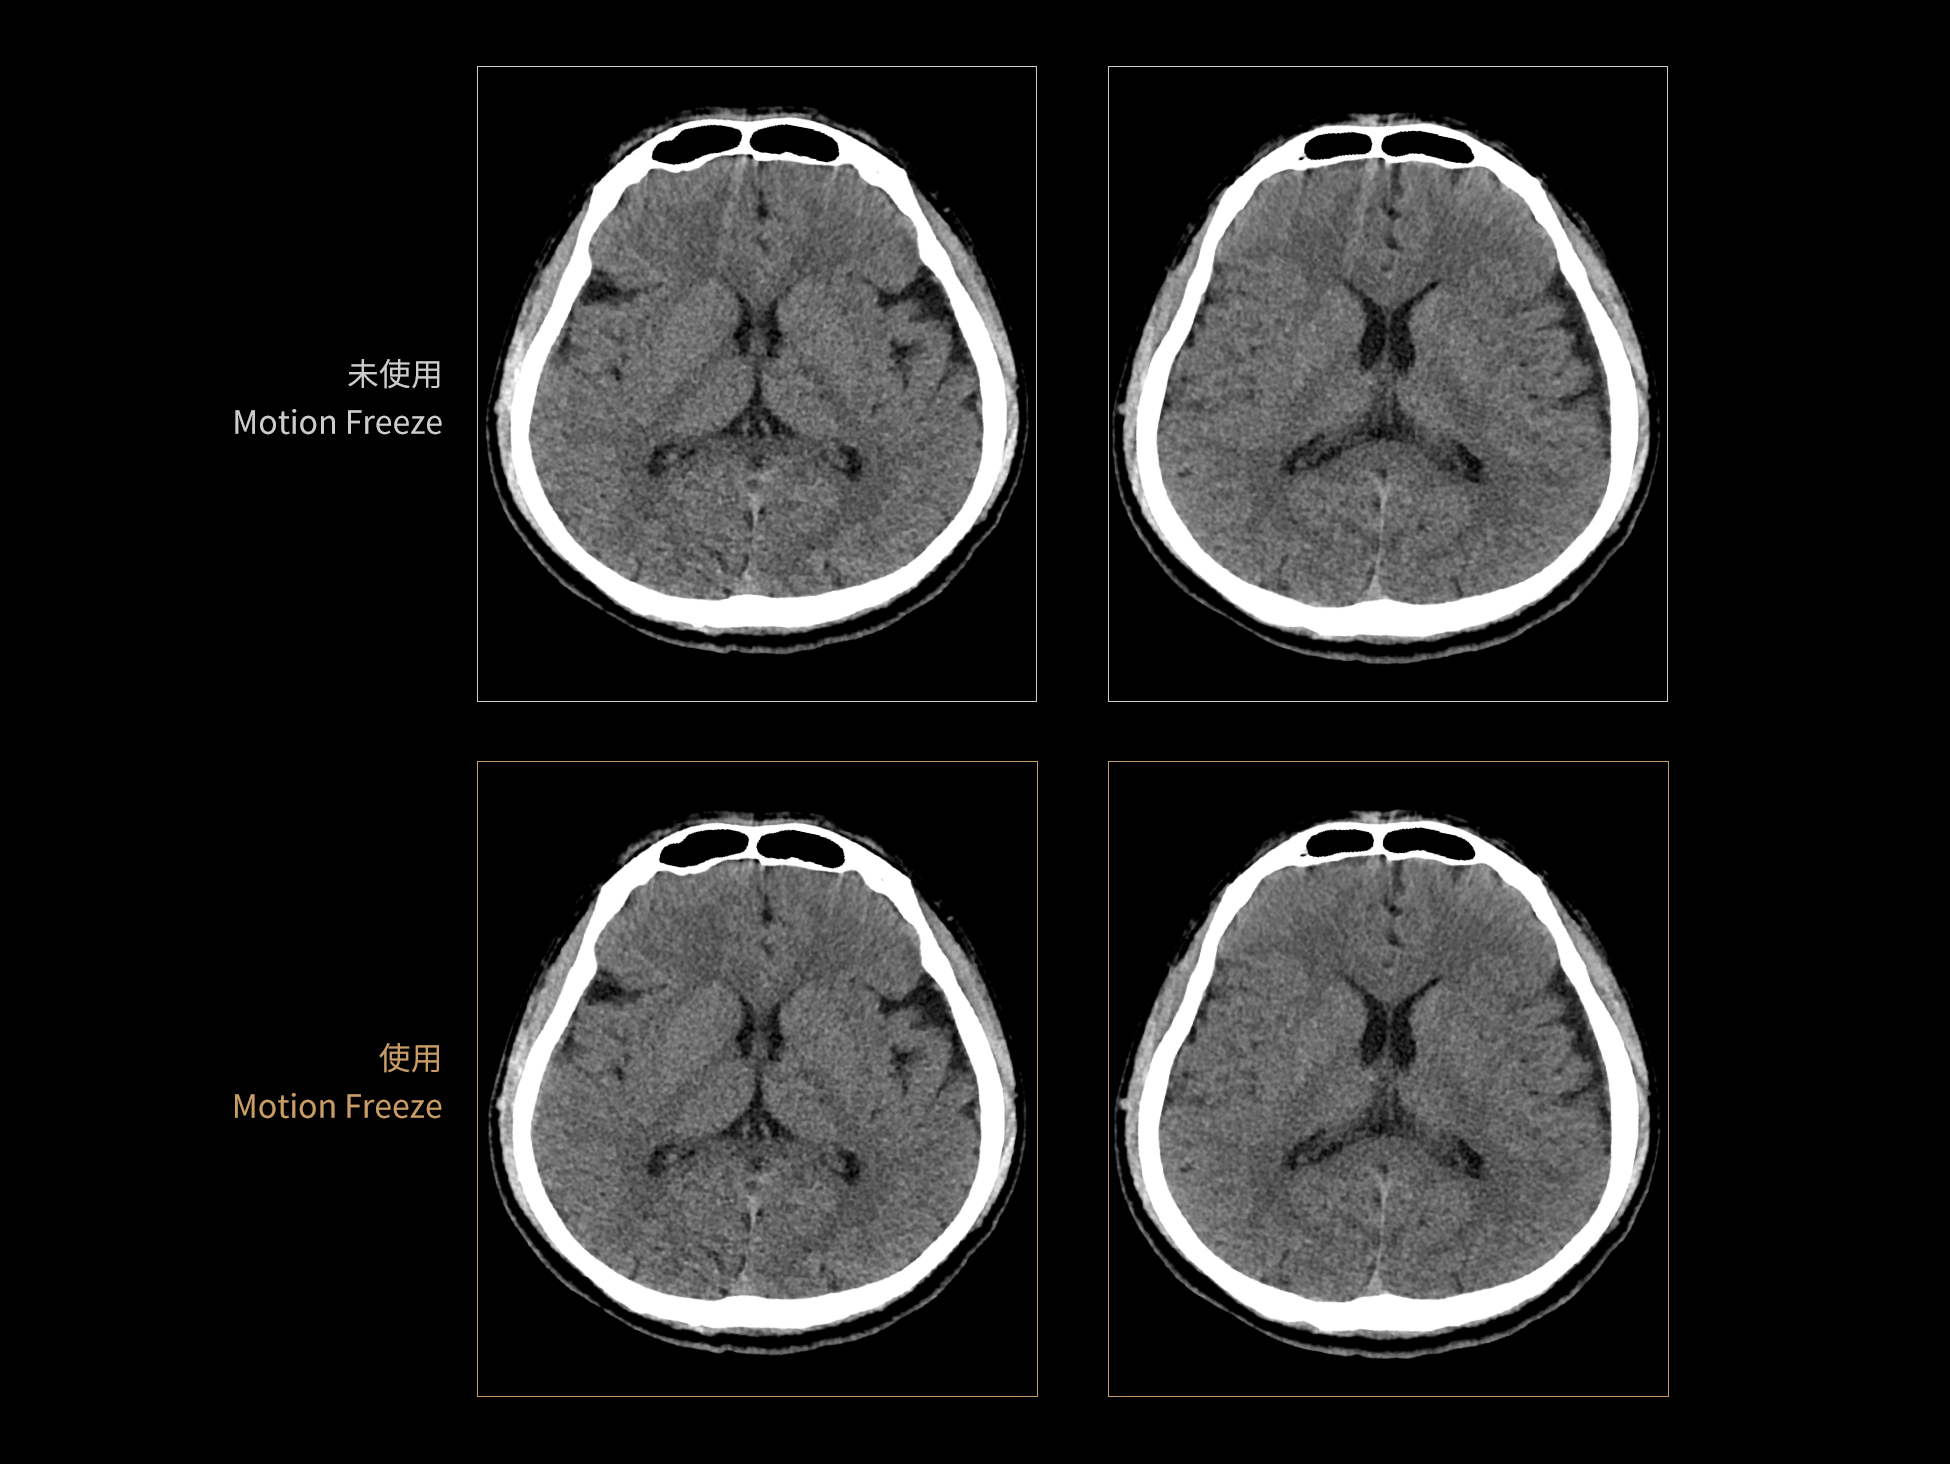

Motion Freeze: 深度学习头部运动伪影校正算法

Motion Freeze 有效抑制头部运动伪影,清晰呈现脑部结构与病灶信息,避免重复扫描,节省检查时间与资源,并降低患者辐射暴露。该算法适用于平扫、增强扫描、CTA 和灌注等多种头部检查模式,显著提升神经系统成像的图像质量与诊断准确性。

支持多种扫描协议下头部运动伪影抑制

三维建模解析真实运动状态

患者头部运动通常呈现多种运动模式,现有算法难以全面消除由此产生的伪影。为构建高质量的训练数据集,Motion Freeze算法在X、Y、Z三个方向上模拟旋转、平移、振荡及多种复合运动场景,系统生成多样化的运动伪影样本。通过引入丰富的运动干扰,该方法使网络模型具备更强的泛化能力,能够应对多种复杂的头部运动情况。